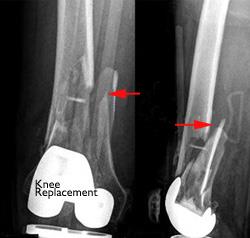

Distal femur fracture near an artificial knee joint

These X-rays taken from the front (left) and the side (right) show a fracture near an artificial knee joint.

Fractures around knee replacements are typically treated with rods or plates, just like other distal femur fractures.

In rare cases, the existing knee replacement must be removed and replaced with a larger replacement. This procedure is called a revision and may be necessary if the implant is loose or not supported by surrounding healthy bone.

Fractures near artificial knee joint treated with internal fixation and revision knee replacement

Fractures near knee implants may be treated with plates, rods, or with a revision surgery.